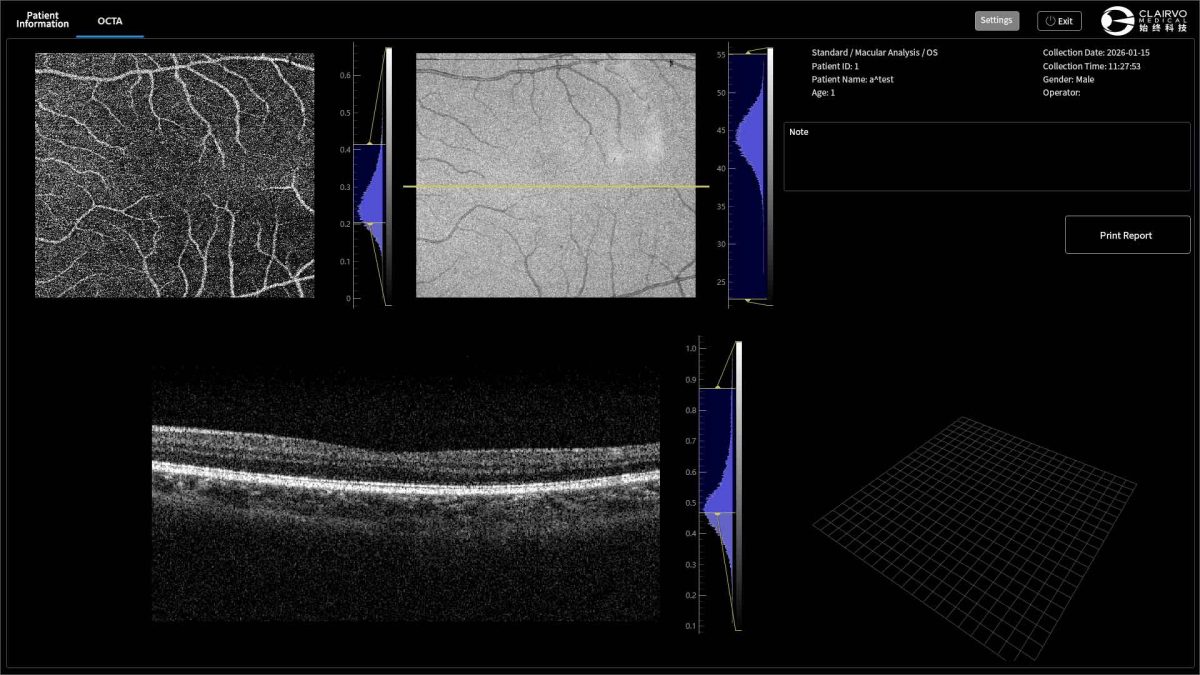

Clear Blood-Flow Imaging

Delivers high-definition OCTA visualisation of microvascular networks,enabling precise detection of choroidal capilary neovascularisatior and enhanced assessment of retinal perfusion.